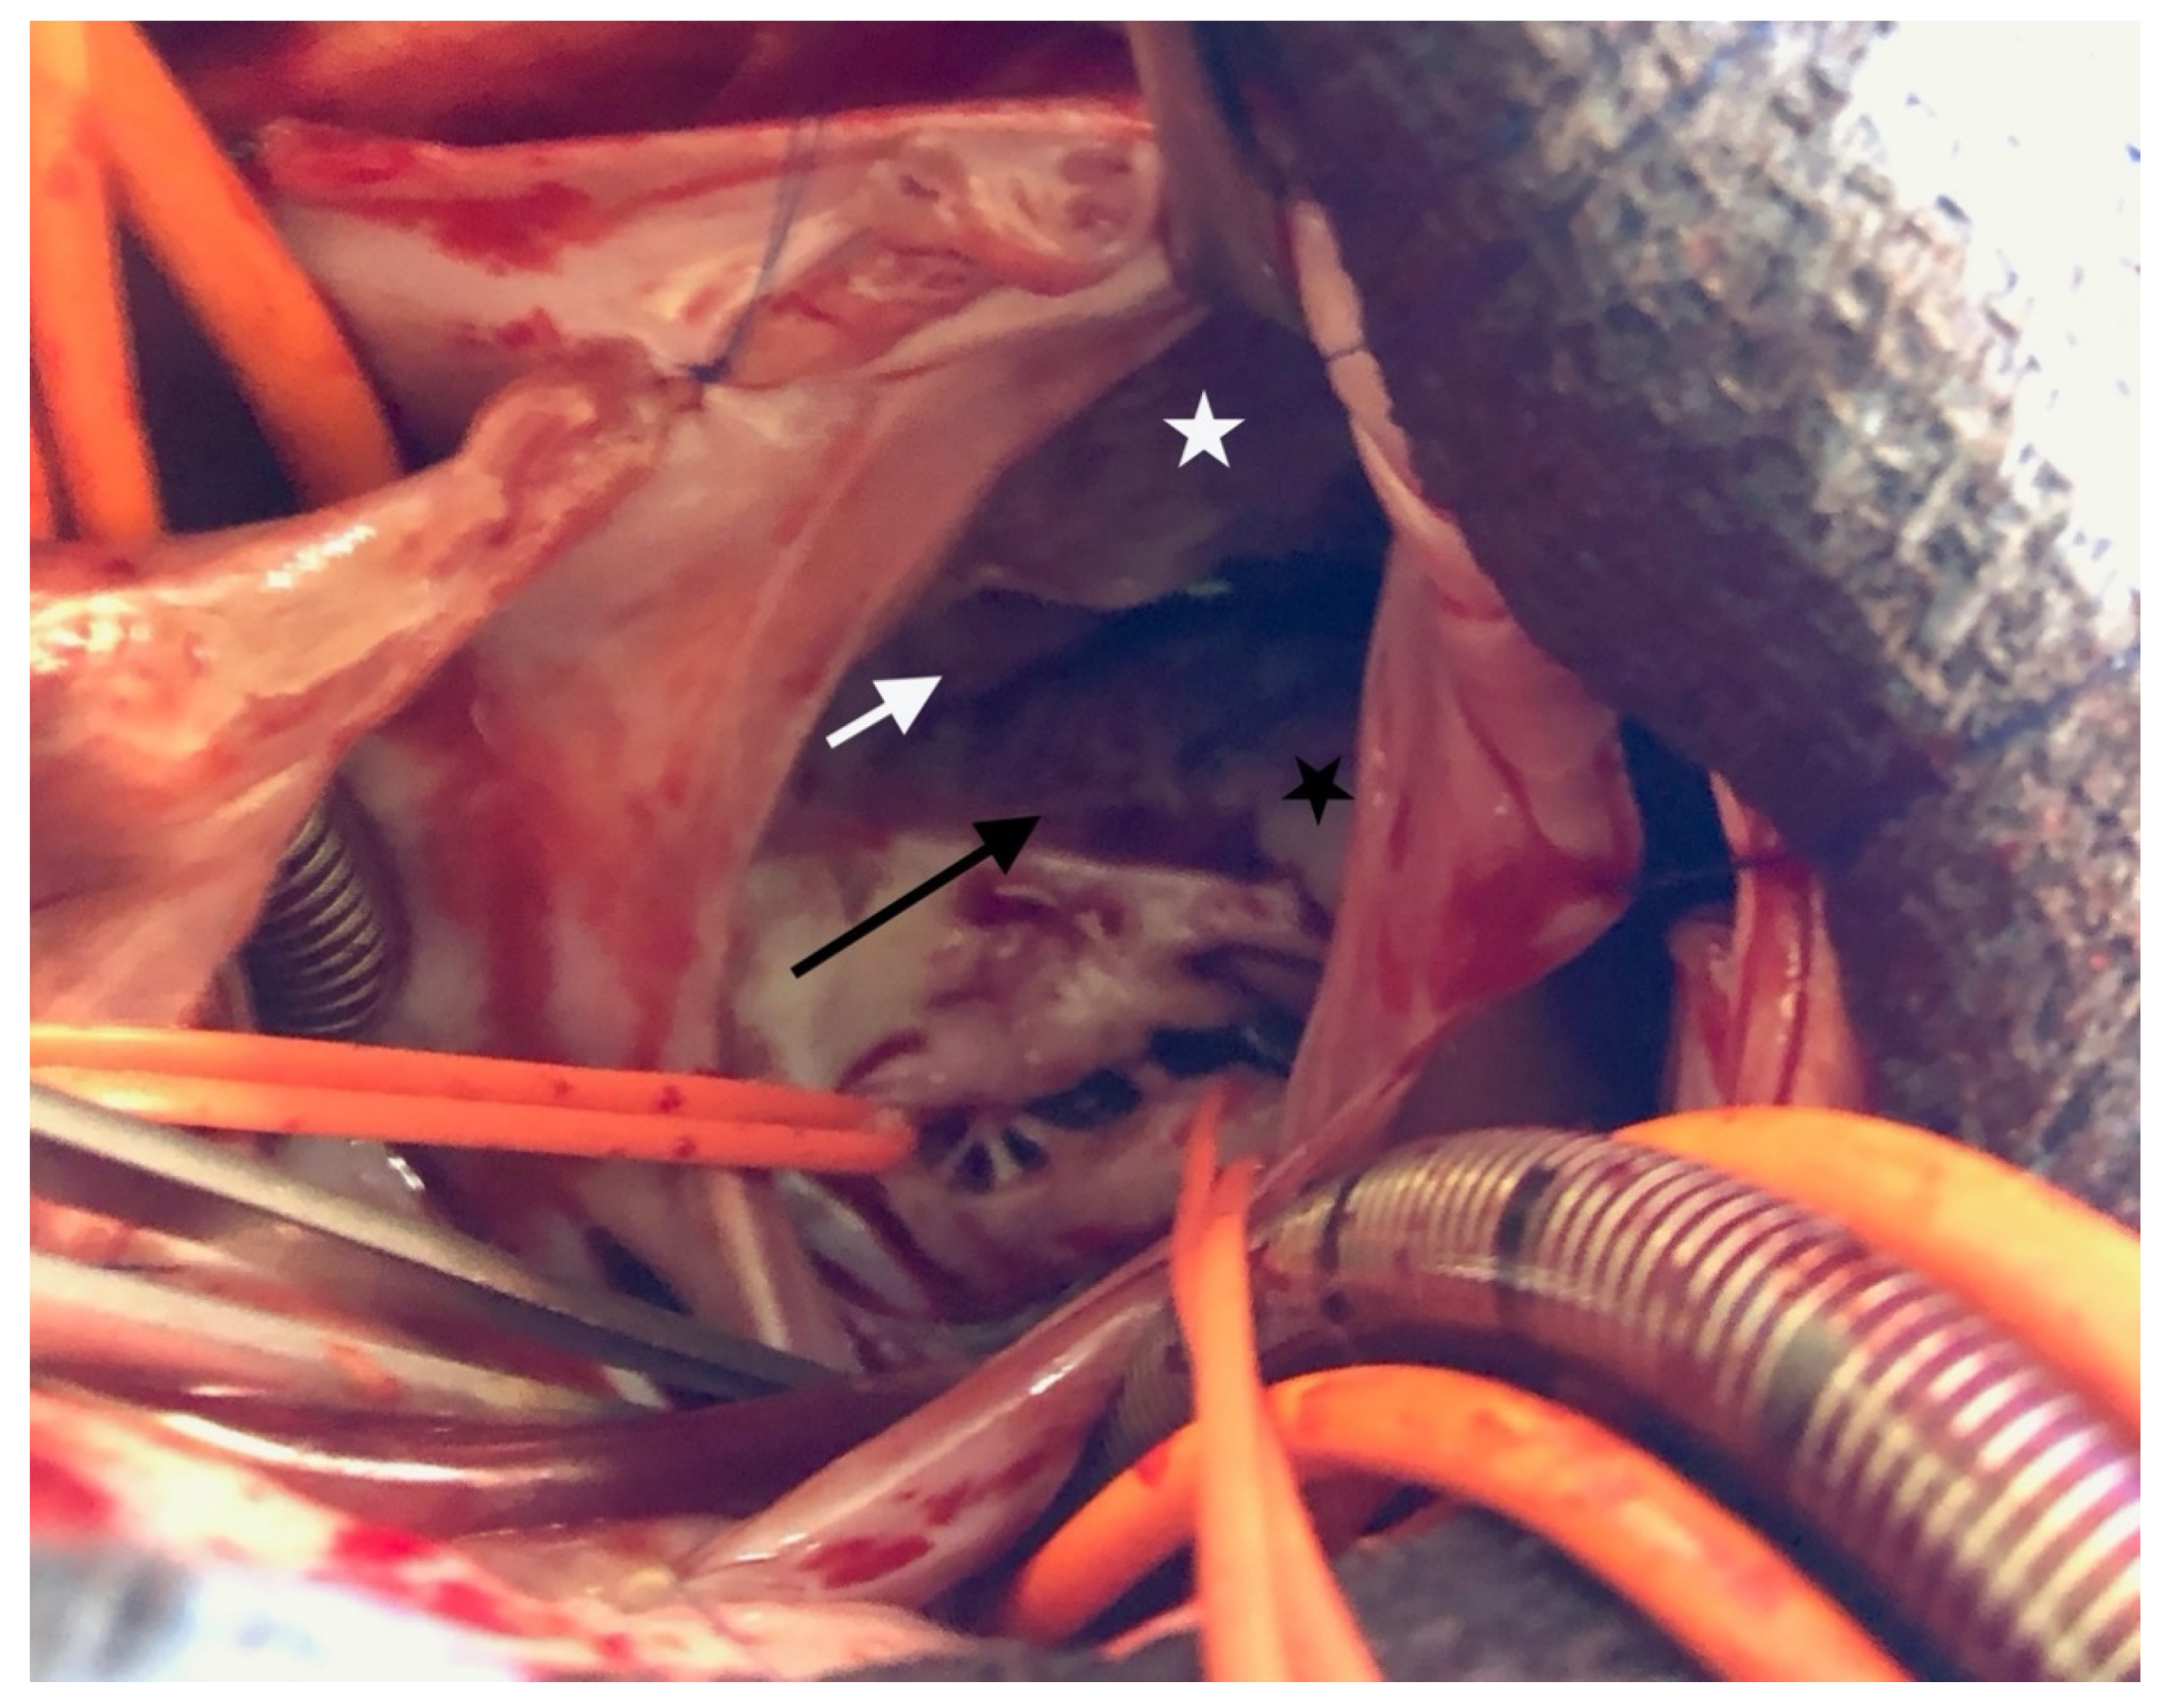

The surgical inspection confirmed the lesions: Ebstein’s disease was atypical and severe and was an intermediate type between B and C [5]. The following description starts from the anteroseptal commissure and goes clockwise: the anteroseptal commissure was very unusual, as if a first part of the anterior valve was missing. A portion of the septal band, the posterior division of the moderator band, reached the atrioventricular valve ring. Then, a small part of the next anterior valve was normally developed. The opening was like the “tricuspid funnel” type and therefore was quite primitively directed towards the infundibulum (Figure 3). Moving to the right and downwards, we quickly found a muscularized valve; then, in some places, a portion was indissociable from the right ventricle (which corresponds more or less to the beginning of the posterior valve, which nevertheless existed), but also, in some other places, was delaminated. Thus, it was unquestionable that it was an Ebstein, although rather atypical. For example, the only real “atrialized” part was in fact at the level of the anterior septal commissure.

Figure 3. Ebstein’s anomaly. White asterisk: delaminated portion of the anterior valve; black asterisk: posterior valve residue, white arrow: “tricuspid funnel” type opening; black arrow: atrialized portion of right ventricle.